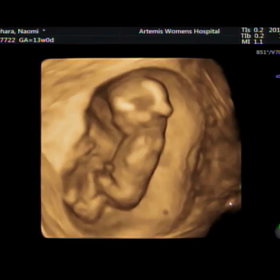

妊婦検診 13w0d 初の3D、4D動画